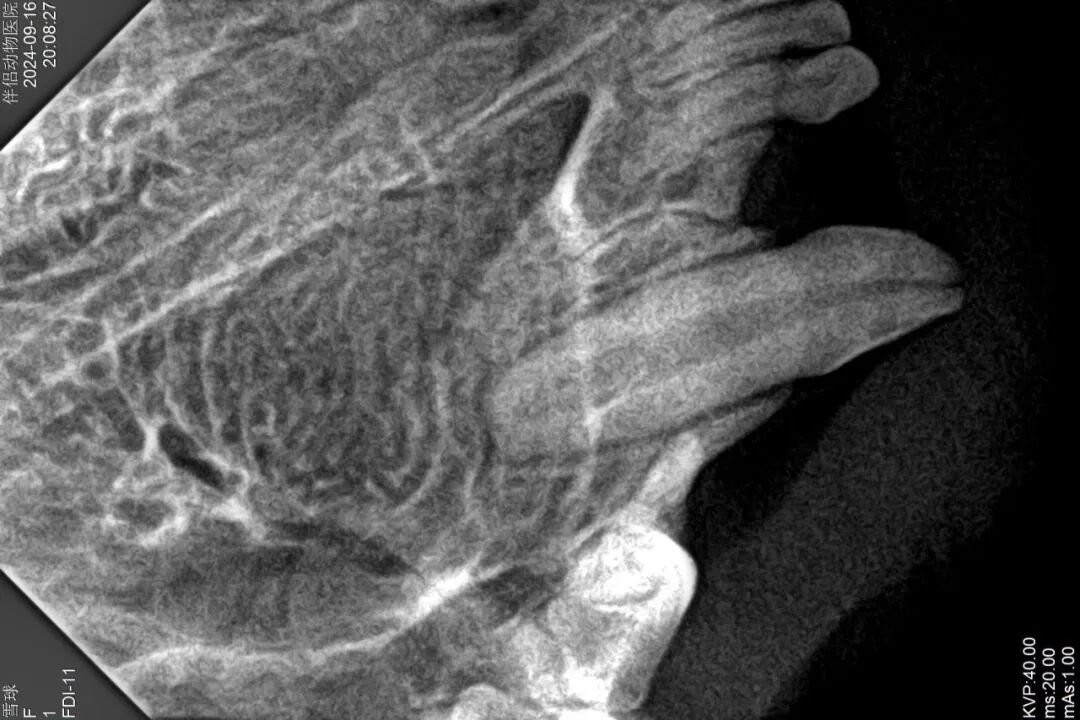

5、术前牙科DR提示根尖闭合、根尖周未见感染

口腔光固化灯是什么光【病例分享】猫-牙科-活髓治疗_https://www.jmylbn.com_新闻资讯_第10张